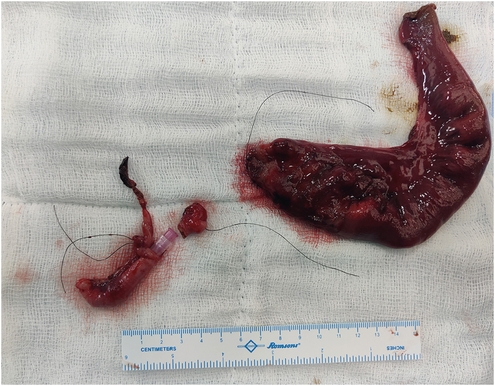

A 5-day, full term, male was referred to us with vomiting which was initially semi-digested milk but become bilious over 24 hours. The baby also developed progressive abdominal distension and non-passage of stools. Clinical examination revealed a moderately dehydrated baby with no meconium per rectum even after a rectal saline wash. No antenatal ultrasound findings were available. Abdominal X-ray was suggestive of multiple dilated bowel loops with air fluid levels (Fig. 1). Exploratory laparotomy was planned with a provisional diagnosis of small bowel atresia.

Fig. 1

Erect X-ray done in Emergency Room showing dilated bowel loops with few air-fluid levels.